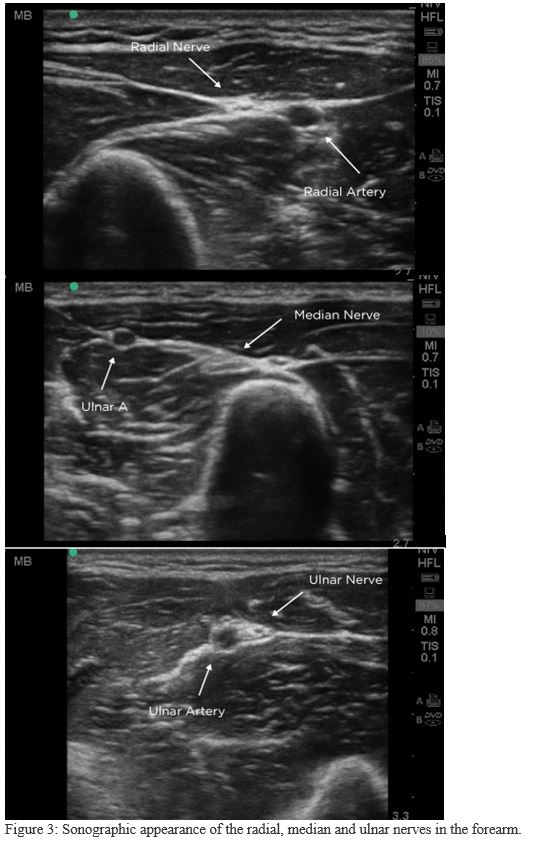

3. Locate the nerves (Figure 3)

Difficulty clearly identifying nerves amongst the other structures is a common frustration. In cross-section on US, a nerve appears as an elliptical bundle containing many small scattered echogenic foci and running within a fascial plane. These blocks are best performed in the mid-forearm. The distal forearm has many tendons which may be mistaken for nerves and in the proximal forearm the nerves are deeper making them more difficult to target.

Finding the radial nerve:

- Find the radial artery in cross section at the wrist.

- The radial nerve is seen adjacent to the artery on the radial side.

Finding the median nerve:

- Start with probe centered on volar wrist and move proximally to mid-forearm.

- The median nerve can be visualized between flexor digitorum muscles.

Finding the ulnar nerve:

- Find the ulnar artery in cross section at the wrist.

- The ulnar nerve is seen adjacent to the artery on the ulnar side.